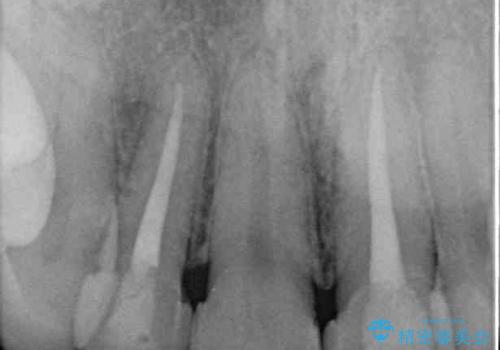

- 前歯のセラミッククラウンが欠けてしまったとのことで来院された患者様です。

周りの他の歯もセラミッククラウンやラミネートベニアが装着されていたため、欠けてしまったクラウンを丁寧に取り外し、同じような色合いとなるように製作することとしました。

欠けたセラミッククラウンを丁寧に外して技工所に送ったことで、元のセラミッククラウン同様の色合いとなり、自然な仕上がりとなりました。